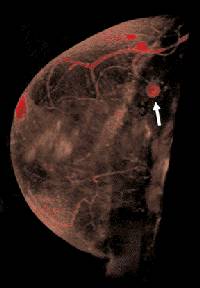

Breast MRI is playing an increasing role in imaging breast cancer (see textbook article) and review article here. There are some concerns that routine MRI results in needless mastectomies (go here).

An MRI will show normal anatomy well (here)

and is helpful in following women who have had surgery (here) and radiation (here). In

young women with dense breasts, it may be difficult to identify a small breast cancer on a

mammogram. There is increasing evidence that an MRI be more sensitive in the early

diagnosis of breast cancers as noted below and go

here. MRI is superior in finding DCIS

(go here). |